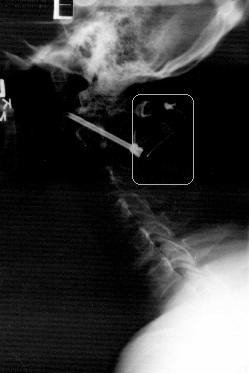

I wasn't too successful in scanning the x-ray. I will continue to try to improve on it. You can obviously see the screws (one in the foreground, one in the rear) that were affixed through C2 into C1 to hold them firmly together while the bone graft fuses. Unfortunately, what you really cant see is the graft itself, the important key element of the procedure. I added the rounded rectangle to add emphasis to where your eyes should be affixed. You can barely make out some wire. That's exactly what that is-thin gauge metal wiring used to wrap the bone taken from hip to the rear of the vertebrae at C1/C2. My misunderstanding is that the graft would be fitted in between the vertebrae. The bone, which is slightly larger than one of my thumbs (yes, one of MY thumbs) was actually grafted to the rear of C1 and C2 where if you could see it more clearly (again my apologies) you would think I would have a lump on the back of my neck at the base of my skull. Anyway, until I find a way to get a better film, this is the basics for you that were curious.